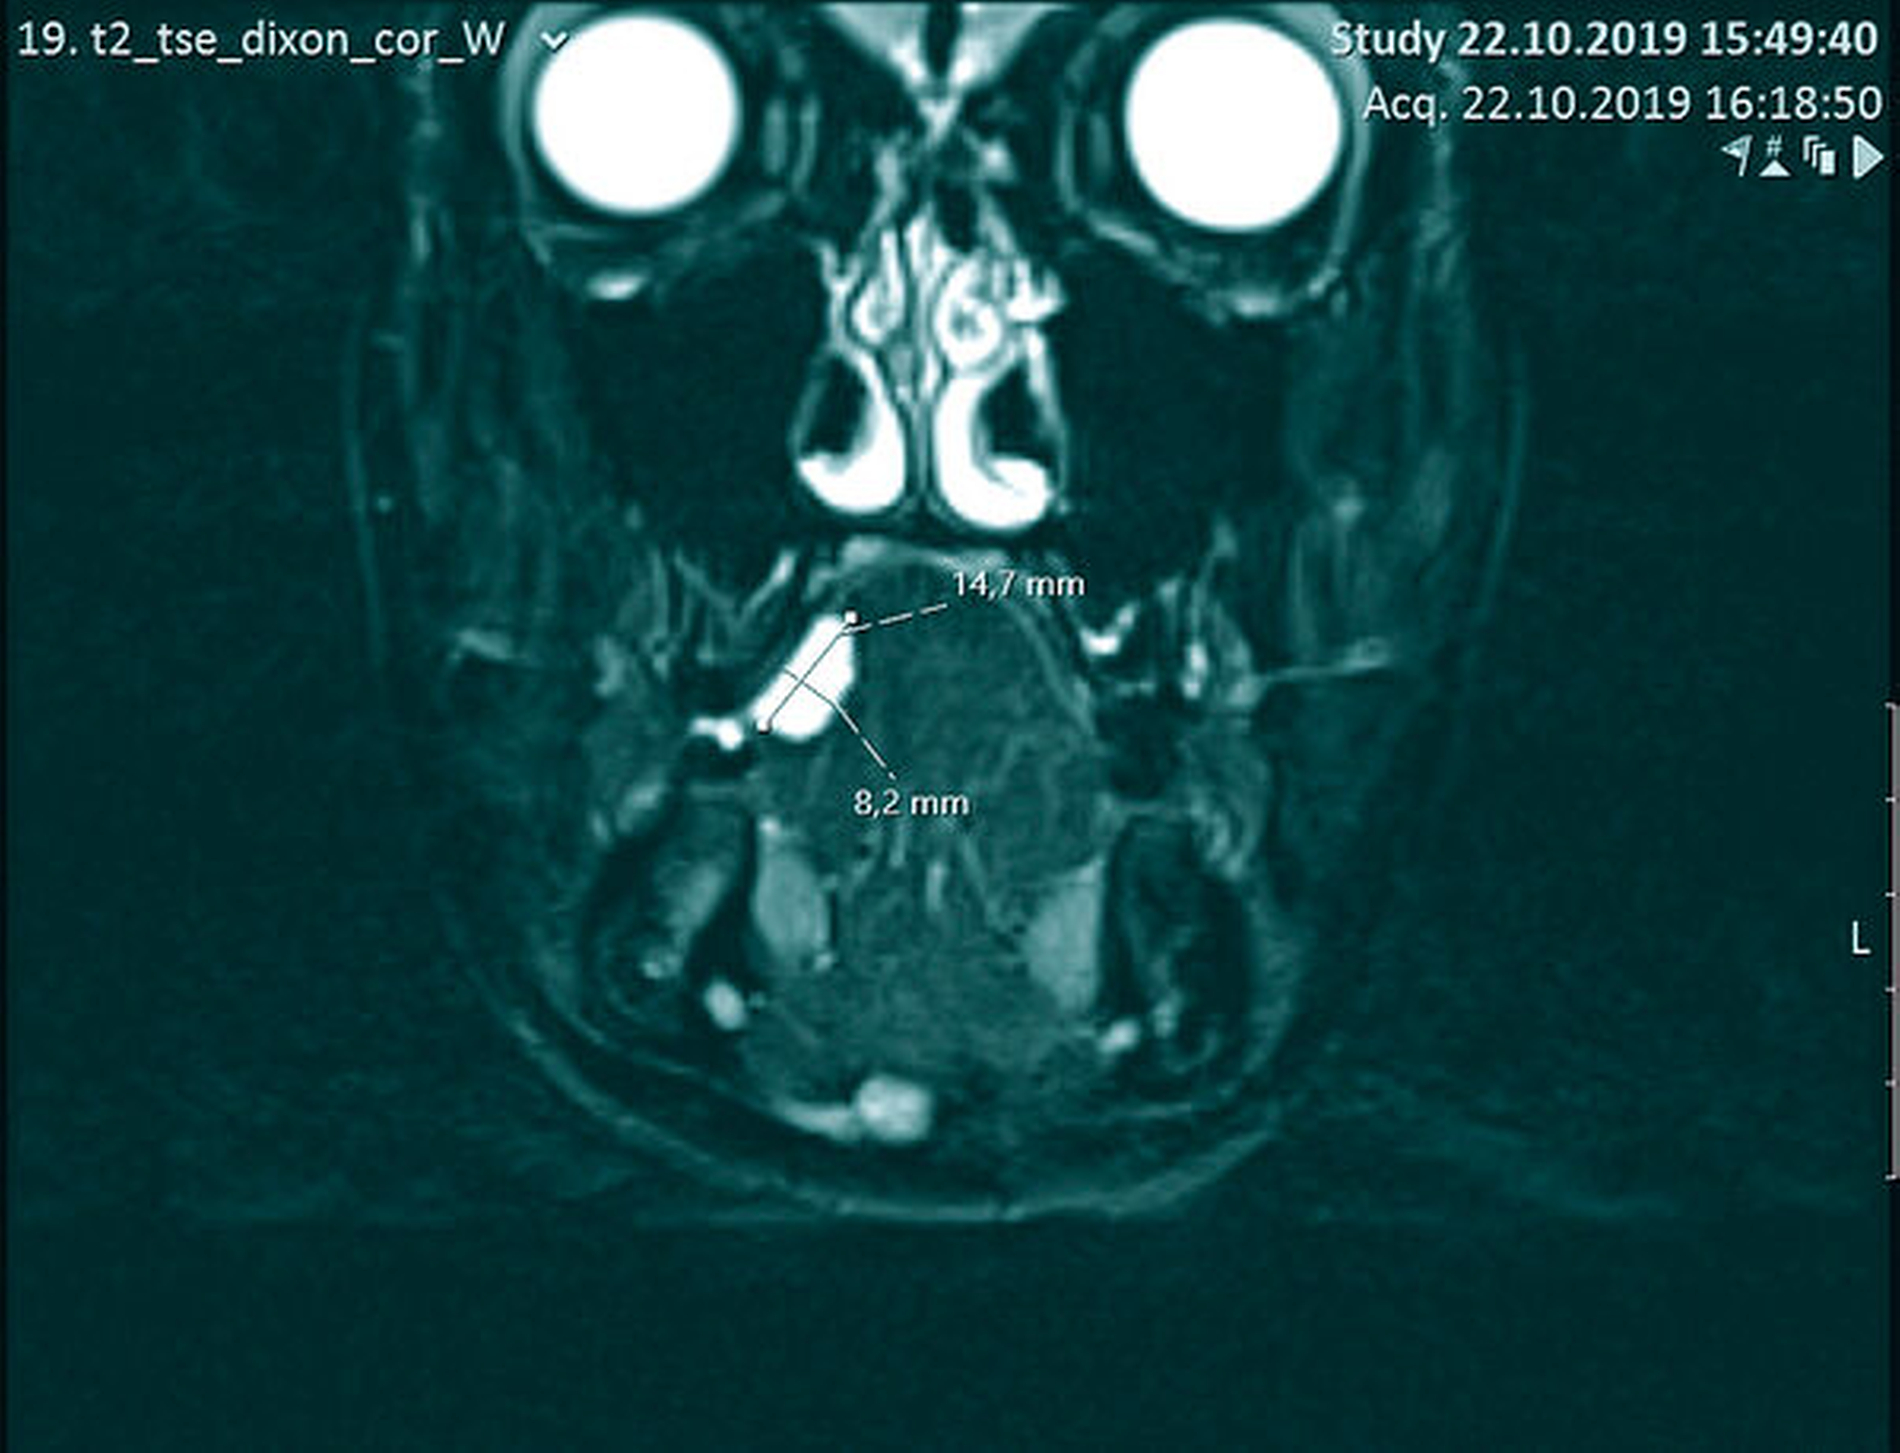

Palpatorisch stellte sich die Raumforderung kugelig-elastisch dar und ließ sich bidigital komprimieren. Das dunkelrot bis violett durchschimmernde Kolorit führte in Zusammenschau mit der Anamnese zu dem Verdacht des Vorliegens einer vaskulären Malformation (Abbildung 1). Beim Ultraschall ließ sich im Duplex-Scan ein niedriger Flow in der Läsion nachweisen, der die Verdachtsdiagnose erhärtete (Abbildung 2). Zusätzlich wurde bei der Patientin eine Magnetresonanztomografie (MRT) mit Kontrastmittel zur Gefäßdarstellung angefertigt (Abbildung 3), wobei man auch hier (wie im Ultraschall) keine größeren zuführenden Gefäße ausmachen konnte.

Zur primären Diagnostik wird vorrangig die Sonografie herangezogen. Speziell mit der Duplex-Sonografie lässt sich ermitteln, ob es sich um eine Malformation mit hoher Durchblutungsrate („high-flow“) oder eher niedriger Flussrate („low-flow“) handelt – ein Fakt, der mit über die weitere Therapie entscheidet [Bodem et al., 2013]. Weiterführend können MRT-Bilder zur Bestimmung der Ausdehnung, zur Abgrenzung von Nachbarstrukturen und zur Darstellung von efferenten und afferenten Gefäßen und somit zur Planung einer potenziellen Embolisation hilfreich sein [Wassef et al., 2015]. Eine Darstellung mit CT und Angiografie ist auch möglich.